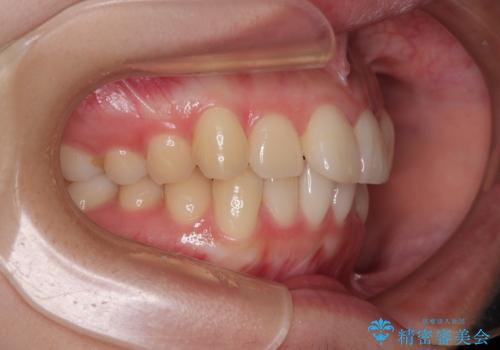

- 上下前歯のデコボコを気にして来院された患者様です。

ワイヤー矯正でもマウスピース矯正でも可能でしたが、短期間で、自身の手を煩わせることなく治療を行いたいとのことで、ワイヤー装置にて矯正治療を行うこととしました。

舌の突出癖により、出っ歯仕上がりとなる可能性がありましたが、舌のトレーニングを頑張っていただき、1年強で終えることができました。